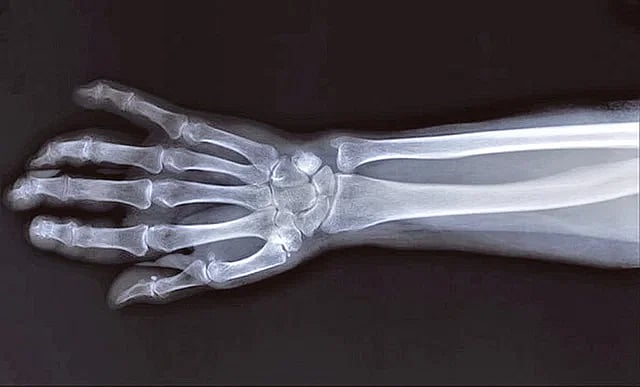

বিশ্বজুড়ে চিকিৎসাবিজ্ঞানে এখন যে এক্স-রে ব্যবহার করা হয়, সেটা শুরু হয়েছিল ১৮৯৬ সালের ১১ জানুয়ারি। ব্রিটিশ চিকিৎসক জন হল-এডওয়ার্ড প্রথমবারের মতো চিকিৎসায় ব্যবহারযোগ্য এক্স-রে উদ্ভাবন করেন। জন হল একজন রোগীর হাতের এক্স-রে করতে গিয়ে প্রথম এটার ব্যবহার করেন।